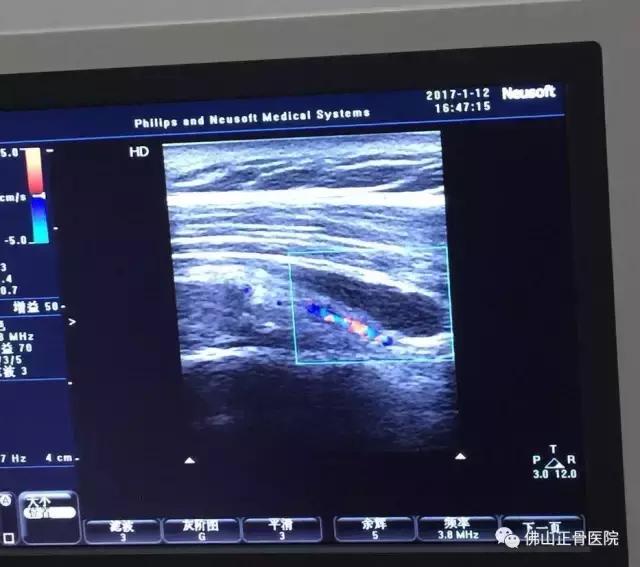

原来困扰刘女士的症状为左肩袖损伤。在超声仪器下,曾主任看见了刘女士肩膀下面的肌腱撕裂和积液,确诊病因后,他随即为刘女士做了超声介导下注射治疗。后经综合治疗2周后,刘女士左肩疼痛基本改善,穿衣等日常活动也恢复正常。

肌骨超声最重要的应用——超声引导下注射治疗!

作为肌肉骨骼疼痛的主要治疗手段,肌骨超声可以进行病变边界定位、深度判断乃至协助引导穿刺活检、抽吸或药物注射治疗。可对关节腔积液及周围囊肿(腱鞘囊肿、腘窝囊肿等)抽吸、肌间血肿(如网球腿形成的血肿)进行抽吸并能促进撕裂肌肉腱膜修复。

一些肌骨方面的慢性疼痛(诸如肩袖腱病、网球肘、高尔夫球肘、跟腱末端病、跖腱膜炎等)进行超声引导下药物注射,同时,在痉挛治疗中也有显著优势,在超声引导下可以实时监测到药物注射到靶肌肉内,对一些深部的肌肉注射具有独特的优势,比常用痉挛注射治疗方法:徒手被动牵伸法、肌电引导法、电刺激引导法更精准,且安全、高效。